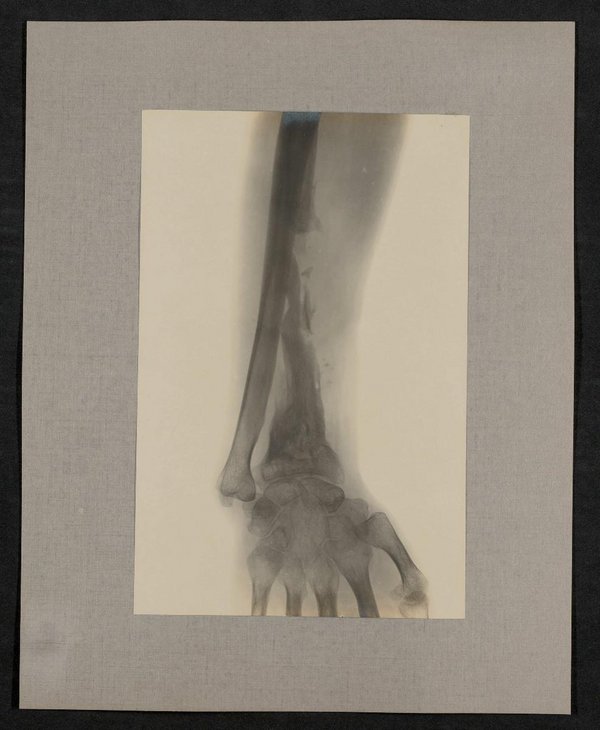

Inventarnummer

AT-MUW-FO-000670-0885-0011

Medizinisches Fachgebiet

Militärmedizin

Datierung

05.09.1915

Ort

Maße

Bildmaß 14,7 x 22,4 cm

Bildmaß inkl. Untergrund 24,7 x 30,7 cm